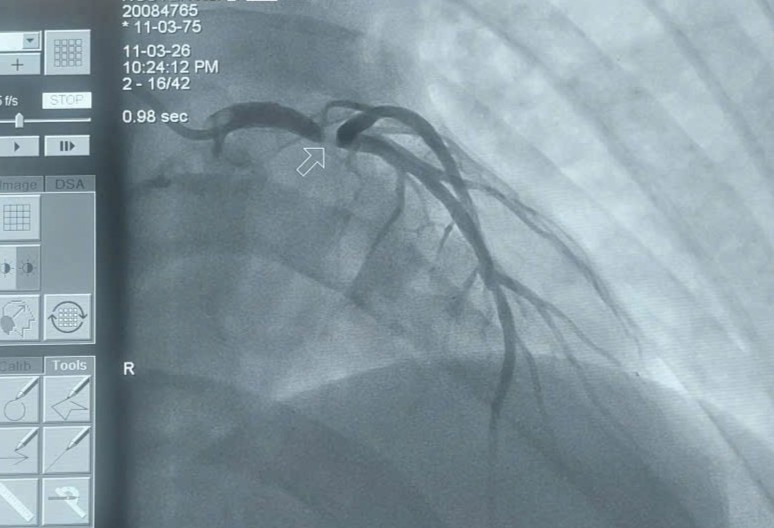

Hình ảnh hẹp thít chân chung động mạch vành trái. Ảnh: BVCC.

Kết quả chụp mạch vành cho thấy bệnh nhân bị hẹp khít thân chung động mạch vành trái. Các bác sĩ đã đặt một stent từ thân chung động mạch vành trái đến động mạch liên thất trước (LM–LAD). Những nhánh mạch vành còn lại chỉ hẹp mức độ vừa và được điều trị nội khoa.